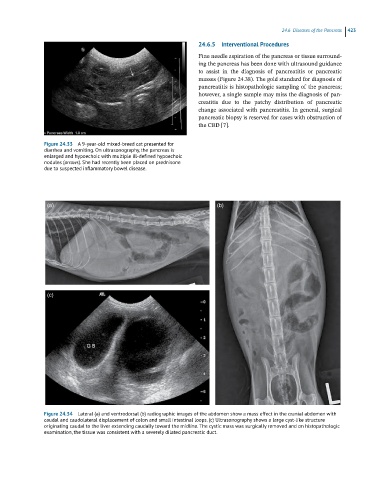

Figure 24.33 A 9-year-old mixed-breed cat presented for

diarrhea and vomiting. On ultrasonography, the pancreas is

enlarged and hypoechoic with multiple ill-defined hypoechoic

nodules (arrows). She had recently been placed on prednisone

due to suspected inflammatory bowel disease.

Figure 24.34 Lateral (a) and ventrodorsal (b) radiographic images of the abdomen show a mass effect in the cranial abdomen with

caudal and caudolateral displacement of colon and small intestinal loops. (c) Ultrasonography shows a large cyst-like structure

originating caudal to the liver extending caudally toward the midline. The cystic mass was surgically removed and on histopathologic

examination, the tissue was consistent with a severely dilated pancreatic duct.